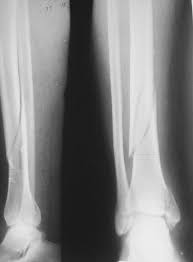

Запитання 19

РОЗПІЗНАЙТЕ КІСТКУ. ПЕРЕЛОМ ЯКОЇ ЇЇ ЧАСТИНИ ВИ БАЧИТЕ НА РЕНТГЕНОГРАМІ?

варіанти відповідей